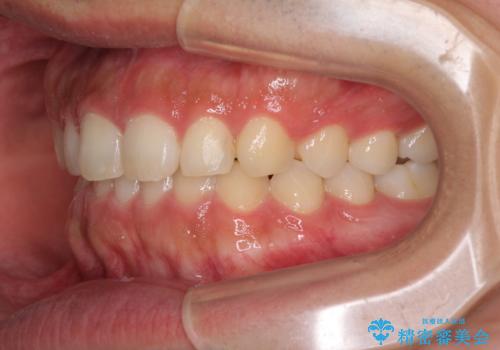

インビザラインによる、すきっ歯の改善

- 前歯がすきっ歯であることを気にして来院された患者様です。

下の前歯がほとんど隠れてしまうくらいの深い咬み合わせであったので、インビザラインを用いて、咬み合わせの高さを改善しながら隙間を閉じていくこととしました。

咬合力で上の前歯が前方に押し出されるようにして隙間ができていましたが、矯正治療により全て閉じることができました。

深い咬み合わせも多少改善され、隙間も閉じたことで、前方に出ていた前歯が引っ込んだため、口も閉じやすくなったとのことでした。